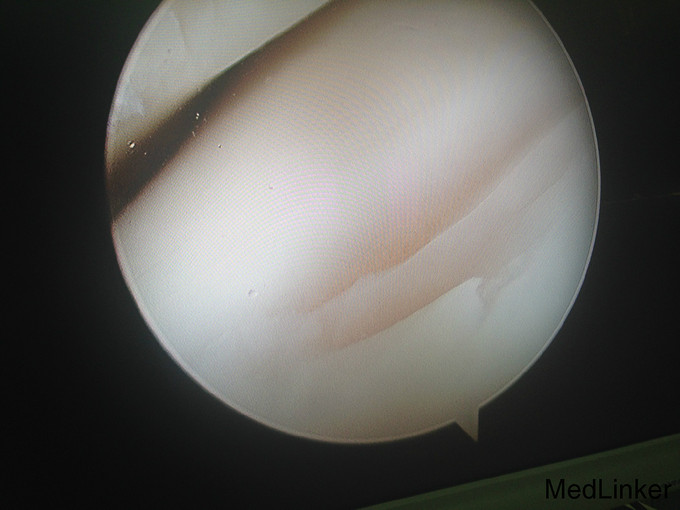

左踝扭伤后肿胀疼痛伴活动受限半年

查体:左腓肠肌萎缩,左踝轻度肿胀。左踝关节ROM较对侧降低,以背伸活动受限最明显。距腓前韧带处未及明显压痛。左踝内、外侧关节间隙压痛(+)。ADT(-),外侧应力试验(-)。左下肢肌张力正常、感觉正常。 辅检:MRI示“左踝关节积液”

诊断:左踝关节创伤性滑膜炎 治疗:左踝关节镜下滑膜清理、胫骨前缘成形

随访:患者术后即刻踝关节活动度恢复正常,2周恢复正常行走。 讨论:踝关节扭伤很常见,扭伤后会发生各种各样的情况。此患者扭伤后继发了滑膜炎,并伤及了关节软骨。这种情况应进行关节镜手术治疗。此外,核磁共振对关节疾患的诊断也是有限的,关节镜才是黄金标准。